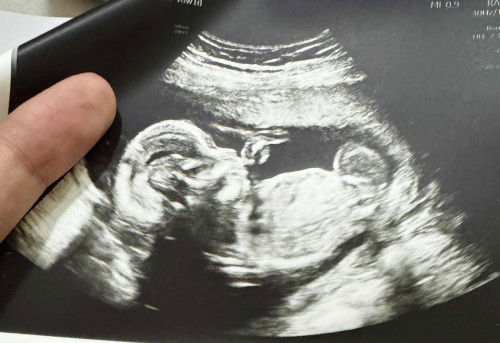

18 weeks scan

Ano pong gender ang sa tingin nyo? 18 weeks po si baby sa tyan ko.